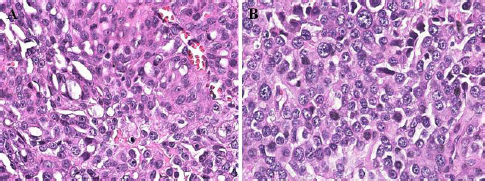

Fig. 2. Histological grading photomicrograph of canine bladder UC. (A) UC with histological grade II (case 11) (H&E, 40× magnification). (B) UC with histological grade III (case 5) (H&E, 40× magnification). Enlarged nucleus, anisokaryosis, and multiple evident nucleoli in grade III are more evident when compared with grade II.

Fig. 3. Histological photomicrograph of invasive canine bladder UC. (A) UC with muscular infiltration (case 21) (H&E, 10× magnification). (B) UC with lymphatic infiltration (case 12) (H&E, 40× magnification).